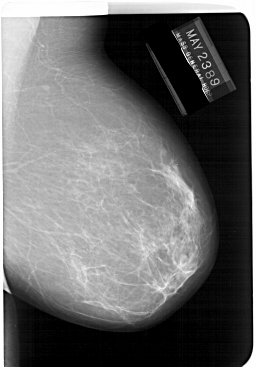

A_1247_1.LEFT_MLO

LEFT_MLO LINES 6226 PIXELS_PER_LINE 4531 BITS_PER_PIXEL 12 RESOLUTION 43.5 OVERLAY